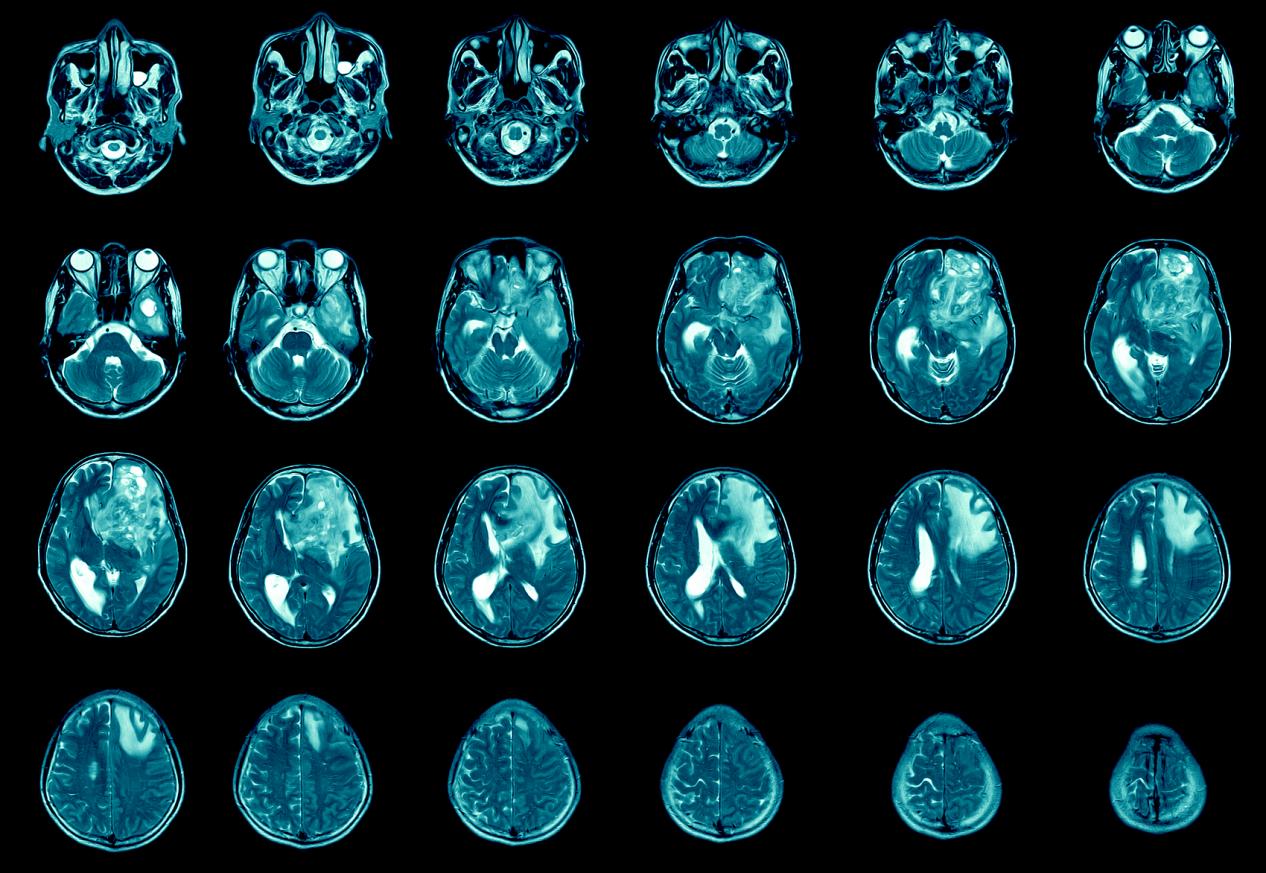

胶质瘤放射治疗是一种常见的治疗方法

胶质瘤放射治疗技术,昆明治疗晚期胶质瘤医院推荐-昆明医科肿瘤医院胶质瘤是一种严重的脑部恶性肿瘤,它起源于神经胶质细胞,通常发生在大脑的深处。胶质瘤的治疗通常涉及手术、放疗和化疗。在这篇文章中,我们将重点介绍胶质瘤放射治疗的相关知识。放射治疗是一种常见的治疗胶质...

胶质瘤放射治疗的适应症有哪些

胶质瘤的早期症状,昆明治疗胶质瘤医院哪家好-昆明医科肿瘤医院胶质瘤是一种常见的脑部肿瘤,通常需要采用综合治疗来控制其生长和扩散。放射治疗作为胶质瘤治疗中的重要手段,可以减少肿瘤的大小和数量,从而改善患者的生活质量和延长生存期。本文将介绍胶质瘤放射治疗的基本情况...

胶质瘤放射治疗的基本原理、治疗方法和注意事项

胶质瘤放射治疗效果,昆明晚期胶质瘤治疗医院推荐-昆明医科肿瘤医院胶质瘤是一种常见的恶性脑肿瘤,常常难以完全切除。放射治疗是治疗胶质瘤的重要手段之一,可以通过辐射杀死肿瘤细胞、抑制肿瘤生长和复发,提高患者的生存率和生存质量。本文将介绍胶质瘤放射治疗的基本原理、治...

胶质瘤放疗相关知识科普

晚期胶质瘤治疗方案,昆明胶质瘤医院效果好的医院-昆明医科肿瘤医院胶质瘤是一种恶性肿瘤,起源于脑中的胶质细胞,是脑肿瘤中最常见的类型。胶质瘤通常会通过手术切除、放疗和化疗等治疗方法进行治疗。其中,放疗治疗在胶质瘤治疗中扮演着重要的角色,本篇文章将会详细介绍胶质瘤...

胶质瘤的治疗效果到底好不好

胶质瘤治疗效果如何,昆明胶质瘤医院哪家还不错-昆明医科肿瘤医院放射治疗是胶质瘤治疗的常用方法之一。下面我们来了解一下放射治疗在胶质瘤治疗中的作用。放射治疗是利用高能射线或粒子对癌细胞进行杀伤的一种治疗方法。放射治疗可以直接杀死癌细胞或阻止它们继续生长和扩散。对...

胶质瘤的治疗方式有哪些

胶质瘤的治疗方式,昆明胶质瘤医院排名推荐-昆明医科肿瘤医院胶质瘤是一种难以治愈的恶性肿瘤,因其高度侵袭性和复发性而难以治疗。目前,治疗胶质瘤的方法主要包括手术切除、放射治疗和化学治疗等综合治疗手段。本文将介绍各种治疗方法的优缺点以及选择治疗方案的考虑因素。手术...

胶质瘤的预后取决于多种因素

胶质瘤的预后效果,昆明胶质瘤医院哪家好-昆明医科肿瘤医院脑胶质瘤是由于大脑和脊髓胶质细胞癌变所产生的、最常见的原发性颅脑肿瘤。年发病率约为3-8人/10万人口。如同其他肿瘤(疾病)一样,胶质瘤也是由于先天的遗传高危因素和环境的致癌因素相互作用所导致的。一些已知...